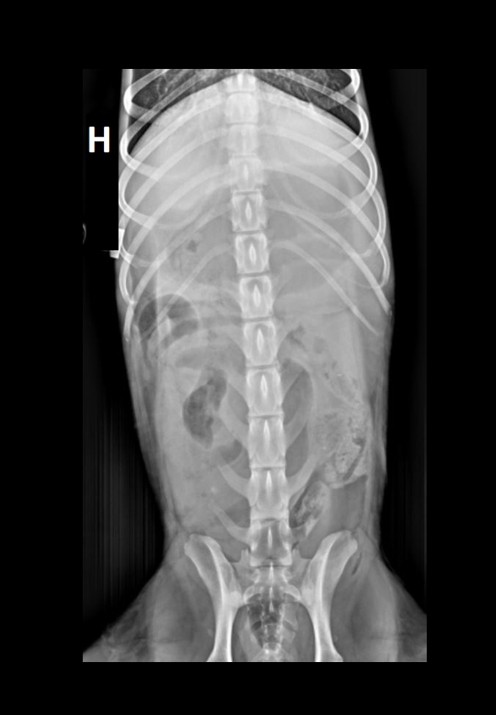

Signalement: Portugisisk vannhund, tispe, 2 år. Anamnese: Oppkast i 2 dager, stort sett uproduktive brekninger siste døgnet. Ingen matlyst eller avføring i disse dagene. Hadde mageproblemer for 2 uker siden, trolig fått i seg pinnekjøtt da. Nedstemt ved ankomst klinikk. Ingen informasjon om siste løpetid.